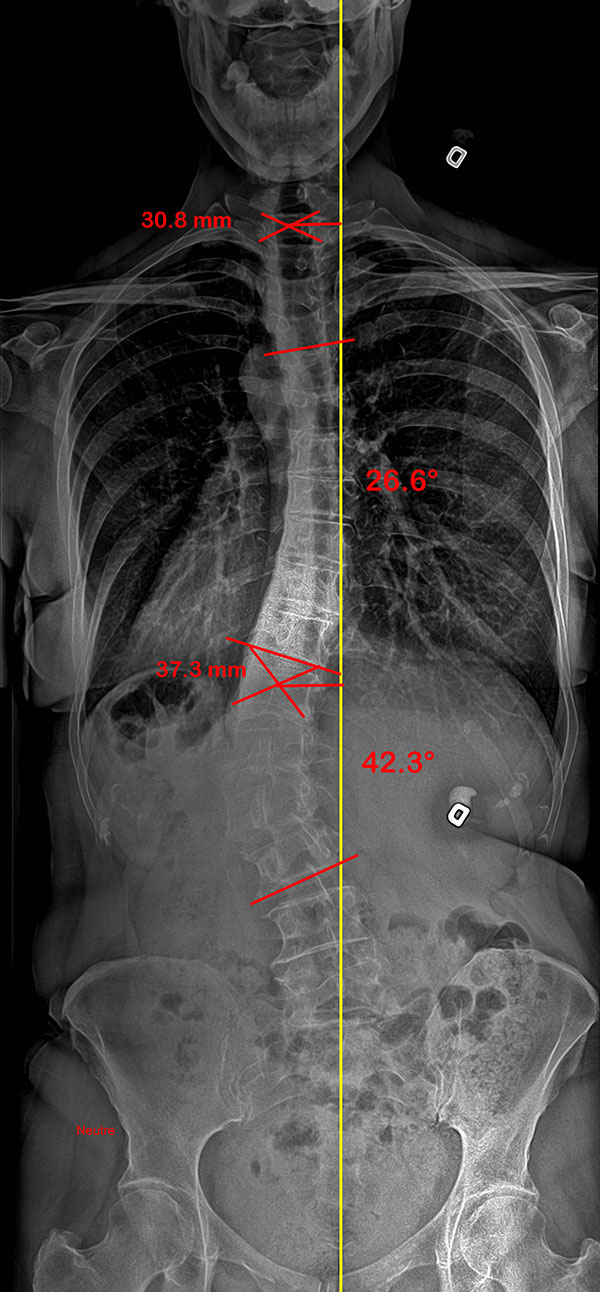

Colonne vertébrale d’un adulte souffrant d’hypercyphose, sans et avec SpineCor®

Radiographies de profil d’un patient présentant une hypercyphose. La ligne jaune représente la courbure idéale et la rouge, celle formée par la colonne vertébrale du patient. Dans la seconde radiographie où le patient porte son SpineCor®, on remarque une amélioration significative de la courbe anormale.